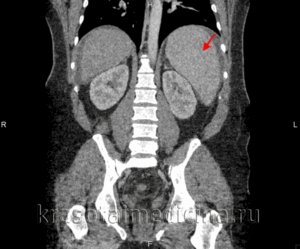

КТ ОБП. Диффузное увеличение печени (зеленая стрелка) и более выраженное увеличение селезенки (красная стрелка).